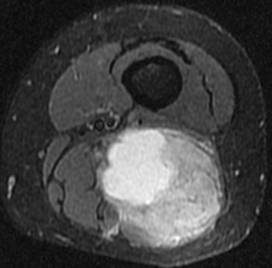

Synovialosarcome. Noter l’aspect hétérogène en T1, T2 et après injection de gadolinium